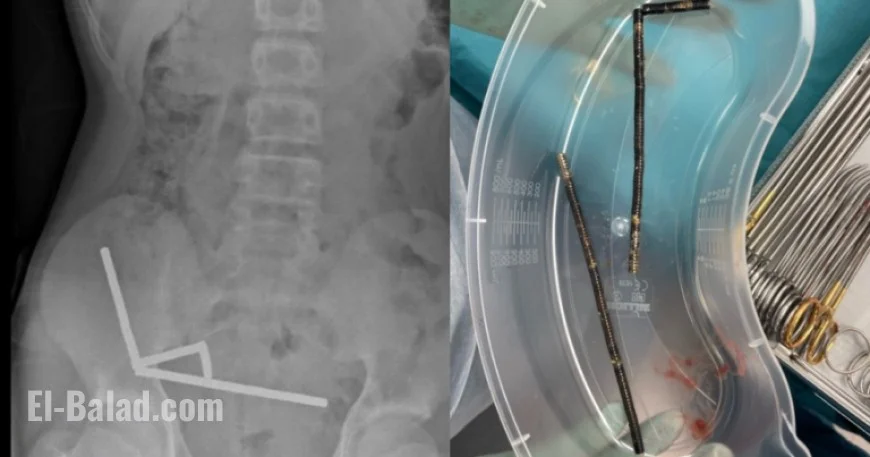

• X-rays showed a dangerous configuration of magnets in his abdomen, forming four chains.

Due to the severity of his condition, an exploratory surgery was performed, during which surgeons successfully removed the magnets and addressed the damaged areas of his bowel. He spent eight days in the hospital recovering before being discharged.